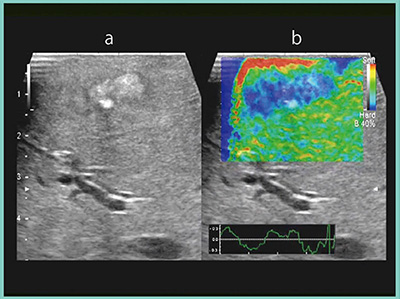

症例2は,異時性単発の肝転移の症例である(図3)。腹腔鏡画像で肝表に突出した白い結節を確認したが,ICG蛍光像で内側に広がる蛍光領域が認められ,こちらが腫瘍本体であると考えられた。RTEでも,蛍光領域と同じ場所に腫瘍が認められた(図3b)。この症例は92歳と高齢のため非常に肝臓がもろく,腫瘍と周辺組織の硬さの差が大きいことから,RTEでは腫瘍が硬い結節として明瞭に描出された。

図3 症例2:肝転移切除(S7/8)のRTE